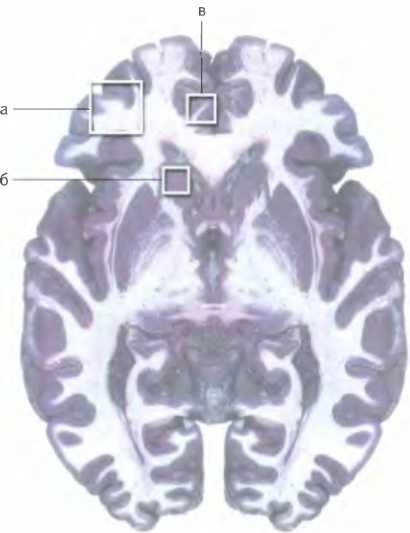

На томограммах головного мозга пациентов, страдающих синдромом Туретта, обычно видна существенно сниженная активность в трех областях мозга: а) дорсолатеральной префронтальной коре, ответственной за произведение уместных действий, б) левых базальных ганглиях, участвующих в управлении машинальными движениями, в) передней поясной коре, помогающей нам концентрировать на своих действиях внимание. Недостаток активности в этих областях приводит к тому, что наружу “прорываются” обрывки неуместных действий — нервные тики. [Источник: Moriarty, J., et a I. Brain perfusion abnormalities in Gilles de la Tourette’s syndrome // British Journal of Psychiatry 167: 2 (1995), pp. 249-254.] У пациентов, страдающих синдромом Туретта, в этих и некоторых других областях мозга обнаруживаются меньшие объемы ткани, чем у здоровых людей, что может быть связано с нарушениями нормального развития определенных нейронных путей2.

Моторными навыками, такими как езда на велосипеде, управляет скорлупа (а) — одна из структур бессознательной лимбической системы. Скорлупа соединена сложной системой связей с премоторной корой (б), входящей в состав сознательной части мозга и вырабатывающей побуждения к движению. Стимуляция скорлупы приводит к тому, что она передает сигнал в премоторную кору, которая, в свою очередь, передает сигнал “двигай” в прилегающую область моторной коры (в). Затем моторная кора посылает сигналы в соответствующие мышцы, вызывая их сокращение. При синдроме Туретта скорлупа гиперактивна, что приводит к регулярной неуместной реализации фрагментов давно освоенных навыков.